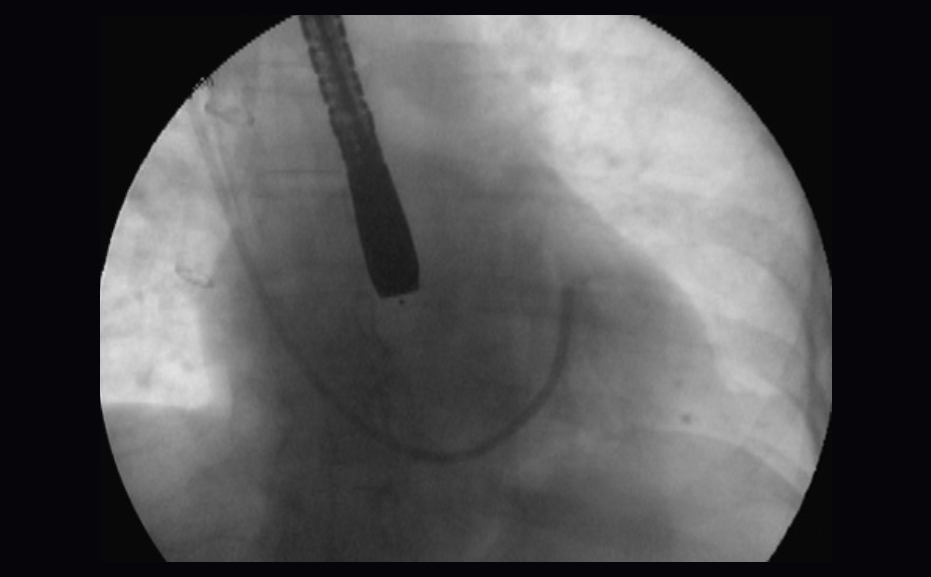

The ProPlege peripheral retrograde cardioplegia device (ProPlege device) is a 9 Fr (3.1 mm), 59 cm long, triple-lumen, articulating device with an elastomeric balloon near its tip for occluding the coronary sinus for retrograde perfusion of the coronary circulation.

- Delivers retrograde cardioplegia through a peripheral approach outside the operating window